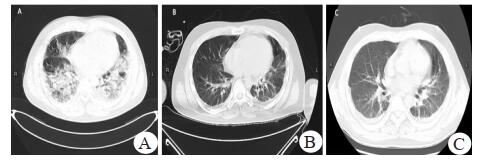

1 资料与方法患者, 男, 29岁, 因发热伴咳嗽、胸闷气喘4 d, 肌肉酸胀1 d于2018年2月入院。入院前4 d受凉后出现咳嗽、咳白痰, 伴有胸闷、活动后气喘, 伴有发热, 最高体温40.6℃, 未予以诊治, 就诊本院当天, 胸闷气喘较前明显加重, 入抢救室后, 查血气PaO2 42 mmHg(1 mmHg=0.133 kPa), SpO2 86%(面罩吸氧10 L/min), 入ICU进一步治疗。查体:T 38.3℃, P 146次/min, RR 40次/min, BP 143/68 mmHg, 神清, 急性面容, 浅表淋巴结未扪及肿大, 口唇发绀明显, 颈软胸廓无畸形, 双肺呼吸音减低, 双肺可闻及散在湿性啰音, 当天尿液呈棕色, 其余指标阴性。部分急查血结果汇报:白细胞(WBC)4.4×109/L, 中性比(Neut)84.3%, 降钙素原(PCT)32.46 ng/mL, C反应蛋白141 mg/L, 肌酐209 μmol/L, 肌红蛋白(MYO)3 890 ng/mL和肌酸激酶(CK)29 699 U/L。入院后肺部CT示:两肺大片状高密度影, 部分实变(图 1A)。追溯病史:患者4年前有吸食冰毒病史, 有幻听幻视症状, 后戒毒, 2016年于外院诊断精神病, 长期服用精神类药物(利培酮1片3 mg/d、氯硝西泮1片2 mg/d、苯海索1片0.5 mg/d控制病情, 已停药1年)。入科后先予以无创呼吸机辅助呼吸(IPAP 14 cmH2O, EPAP 5 cmH2O, FiO2 100%, 1 cmH2O=0.098 kPa), 头孢哌酮舒巴坦联合莫西沙星、奥司他韦抗感染; 但患者高热不退, 复查WBC、Neut、PCT等炎症指标较前明显上升, 且患者频繁咳嗽, 烦躁明显, 难以耐受无创呼吸机, 氧合指数78 mmHg。入科第2天, 予以气管插管接呼吸机辅助呼吸(AC模式f 20次/min, VT 400 mL, FiO2 100%, PEEP 14.0 cmH2O), 联合肌松、镇静、镇痛, 肺复张后氧合状态较前好转, 并联用甲泼尼龙40 mg/d静脉滴注, 用后体温渐降至正常。

| 图 1 患者入院期间的胸部CT(A:患者入院时胸部CT; B:住院第16天的胸部CT; C:患者入院56 d的胸部CT) |

入科后患者呈现无尿状态, 尿液呈棕色, 予以补液水化、碱化尿液, 肾功能未见好转, CR升至617 μmol/L, CK高达36 681 U/L, 入科第3天开始间断行连续性肾脏替代治疗(CRRT)。完善甲型、乙型和丙型肝炎、甲流感病毒、TORCH、EB病毒、CMV病毒、HIV、抗核抗体、ANA、ANCA16项, 痰、血培养均为阴性。血清IgM呈阳性, 支原体效价为1:160, T细胞亚群示CD4+T 60/µL, CD4+/CD8+ T为0.52, 比例倒置。停用奥司他韦, 予以头孢哌酮舒巴坦联合莫西沙星、米诺环素抗感染, 甲泼尼龙抗炎, 同时输注白蛋白、肠内营养、调节肠道菌群、增强免疫等对症。后患者出现凝血功能障碍, 结合入科第6天肺泡灌洗液检出洋葱伯克霍尔德菌, 遂停用头孢哌酮舒巴坦改为哌拉西林他唑巴坦。患者体温基本正常、炎症指标趋于好转, 肺功能较入院时明显改善, 第9天氧合指数可达386.75 mmHg。考虑避免继发性肺部感染, 于第10天行气管切开接呼吸机辅助通气。住院11 d复查支原体抗体滴度与入院第4天比较下降为之前的1/4。故诊断重症MPP、急性呼吸窘迫综合征(ARDS)、RM、急性肾损伤(AKI)明确。然而第12天开始患者反复出现高热, 最高超过39℃, 热前无明显寒战, 血常规、PCT等炎症指标进行性上升, 影像学提示病灶较前明显吸收(图 1B), 动脉血气提示氧合指数尚可, 治疗上增加伏立康唑预防性抗真菌联合替考拉宁兼顾治疗球菌。多次送检痰样本培养检出洋葱伯克霍尔德菌, 据药敏试验结果, 尚可以覆盖病原菌。患者体温、炎症指标水平后下降, 气管切开8 d后顺利脱机拔管序贯高流量吸氧。ICU治疗后期患者痰多次培养检出多重耐药菌肺炎克雷伯杆菌, 调整方案为头孢哌酮舒巴坦联合磷霉素钠、替加环素抗感染, 辅以对症治疗。复查胸部影像学较前改善(图 1C)。T细胞亚群CD4+/CD8+从0.52上升到1.03。患者入科后间断行CRRT治疗, 肾功能于入院28 d恢复。并在入院37 d转回普通病房治疗。患者ICU期间治疗经过、相关肾功能情况如图 2、图 3。普通病房治疗1个月后出院。随访中, 患者的情况稳定。